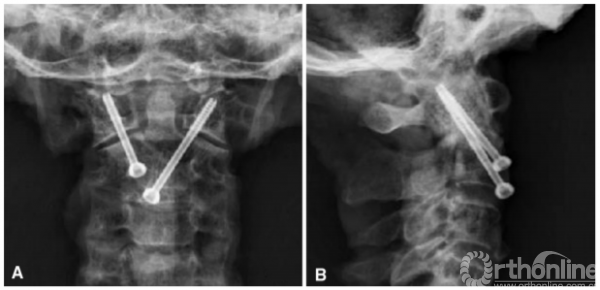

所有标本均成功完成ATCS和ATS固定,未见C1椎动脉沟、椎管及寰枕关节损伤。ATCS和ATS实际进钉点与中线的侧方距离分别为5.0±1.1mm和13.0±1.5mm。ATCS固定理想的外展角和倾斜角分别为38.3±4.1°和30.7±2.9°,而ATS分别为29.6±2.7°和34.3±2.5°。理想螺钉角度与实际螺钉角度无统计学差异(P<0.05)。螺钉置入后(图4),x线测量ATCS相对矢状面实际外展角大于ATS。然而,ATCS相对于冠状面的实际倾斜角小于ATS(表3)。

图4前路经关节交叉螺钉固定前后位x线片(a)和侧位片(b)视图

The ATCS and ATS were inserted successfully into all specimens without any violation to the VA groove of C1and C2, or the spinal canal. Neither was there any violation to the atlanto-occipital joint. The actual entry points of ATCS and ATS lateral from the midline was 5.0 ± 1.1 mm and 13.0 ± 1.5 mm, respectively. The ideal lateral and incline angles were 38.3 ± 4.1 and 30.7 ± 2.9 for the ATCS, and 29.6 ± 2.7 and 34.3 ± 2.5 for the ATS, respectively. There was no statistical difference between the ideal and the actual screw angulations (p<0.05). After the screws were inserted (Fig. 4), the actual lateral angle of the ATCS relative to sagittal plane was greater than that of the ATS measured on anteroposterior X-rays. On the contrary, the actual incline angle of the ATCS relative to coronal plane was smaller than that of the ATS (Table 3).

Fig. 4 The anterior transarticular crossing screws fixation is shown on anteroposterior (a) and lateral radiographs (b), respectively